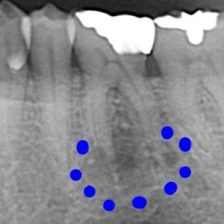

治療の前にはマイクロスコープや一眼レフカメラでお口の中を撮影して、現状をご確認いただきます。さらに患者さまのお悩みやご希望をしっかりうかがい、的確な治療法をご提案いたします。

根管治療

症例集